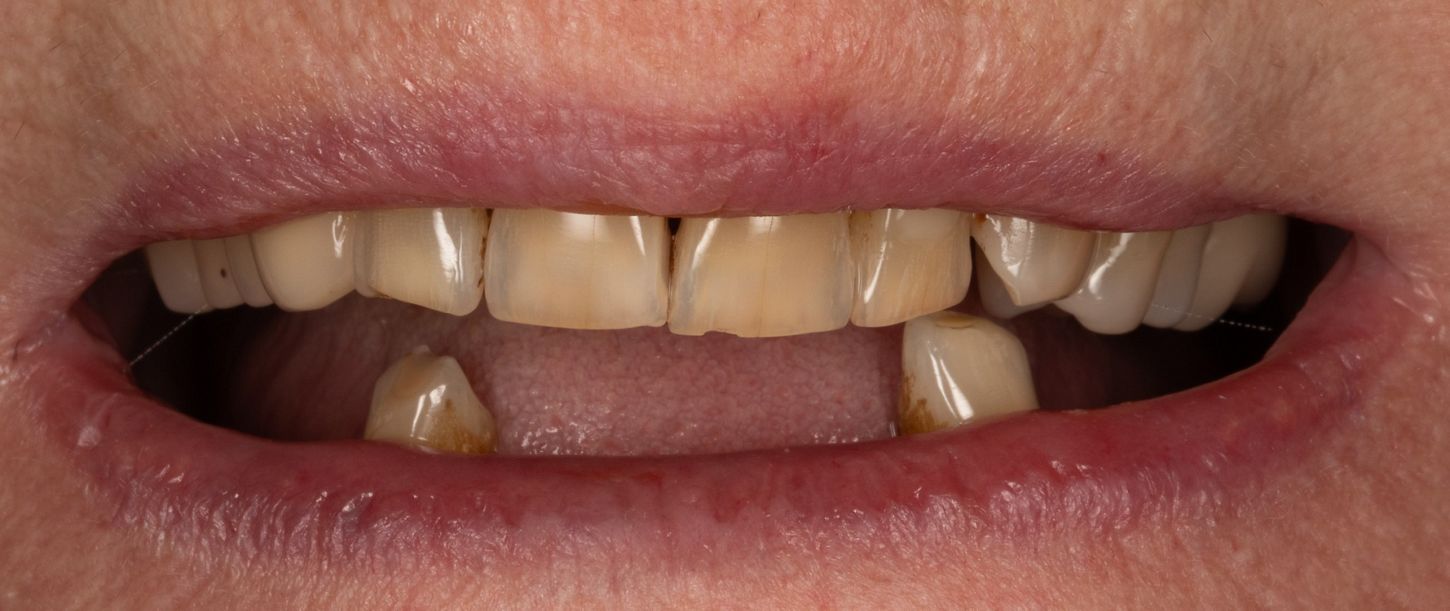

2a. View of the mouth showing limited gingival exposure.

2a

2b. Situation in the maxilla: the periodontal situation is stable.

2b